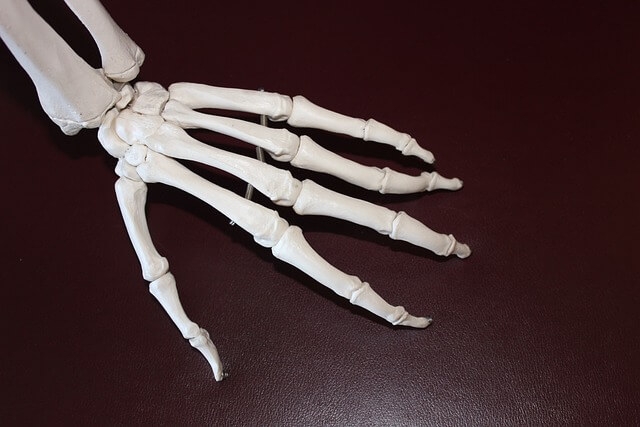

● 갑작스러운 심한 통증: 주로 밤에 시작되며, 엄지발가락이나 발목, 무릎 등에서 발생합니다. 통증은 매우 강하고, 관절이 붓고 뜨겁게 느껴집니다.

● 발적 및 부종: 염증이 생기면 관절 주변이 붉고 부풀어 오릅니다.

● 운동 제한: 통증으로 인해 affected 부위를 움직이는 것이 어려워질 수 있습니다.